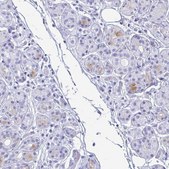

Anti-LTF antibody produced in rabbit

immunohistochemistry: 1:200- 1:500

The Human Protein Atlas project can be subdivided into three efforts: Human Tissue Atlas, Cancer Atlas, and Human Cell Atlas. The antibodies that have been generated in support of the Tissue and Cancer Atlas projects have been tested by immunohistochemistry against hundreds of normal and disease tissues and through the recent efforts of the Human Cell Atlas project, many have been characterized by immunofluorescence to map the human proteome not only at the tissue level but now at the subcellular level. These images and the collection of this vast data set can be viewed on the Human Protein Atlas (HPA) site by clicking on the Image Gallery link. We also provide Prestige Antibodies® protocols and other useful information.

- IHC tissue array of 44 normal human tissues and 20 of the most common cancer type tissues.